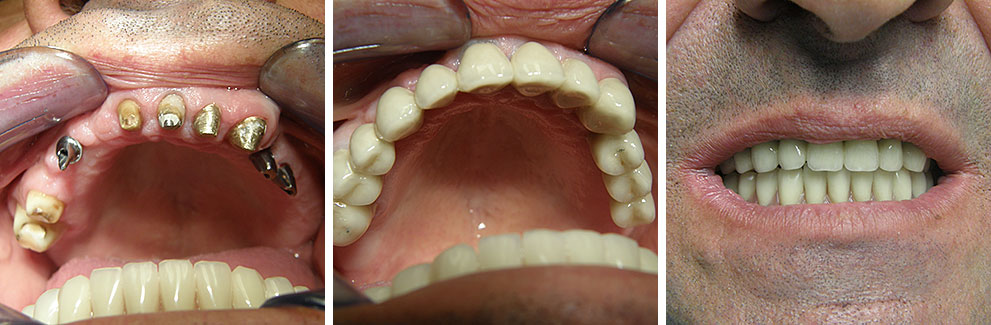

Implantologija